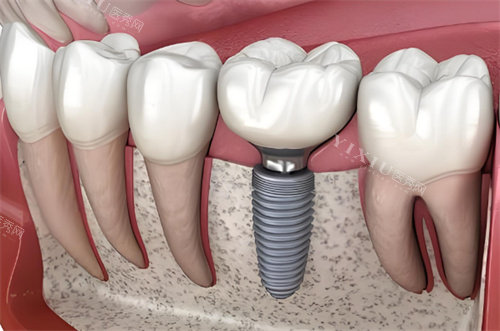

种植牙项目:

即刻种植牙:5980元起

国产创英种植牙:5800元起

韩国登腾种植牙:6200元起

德国BEGO种植牙:8800元起

瑞士ITI种植牙:12800元起

全口种植牙(ALL-ON-4):68000元起